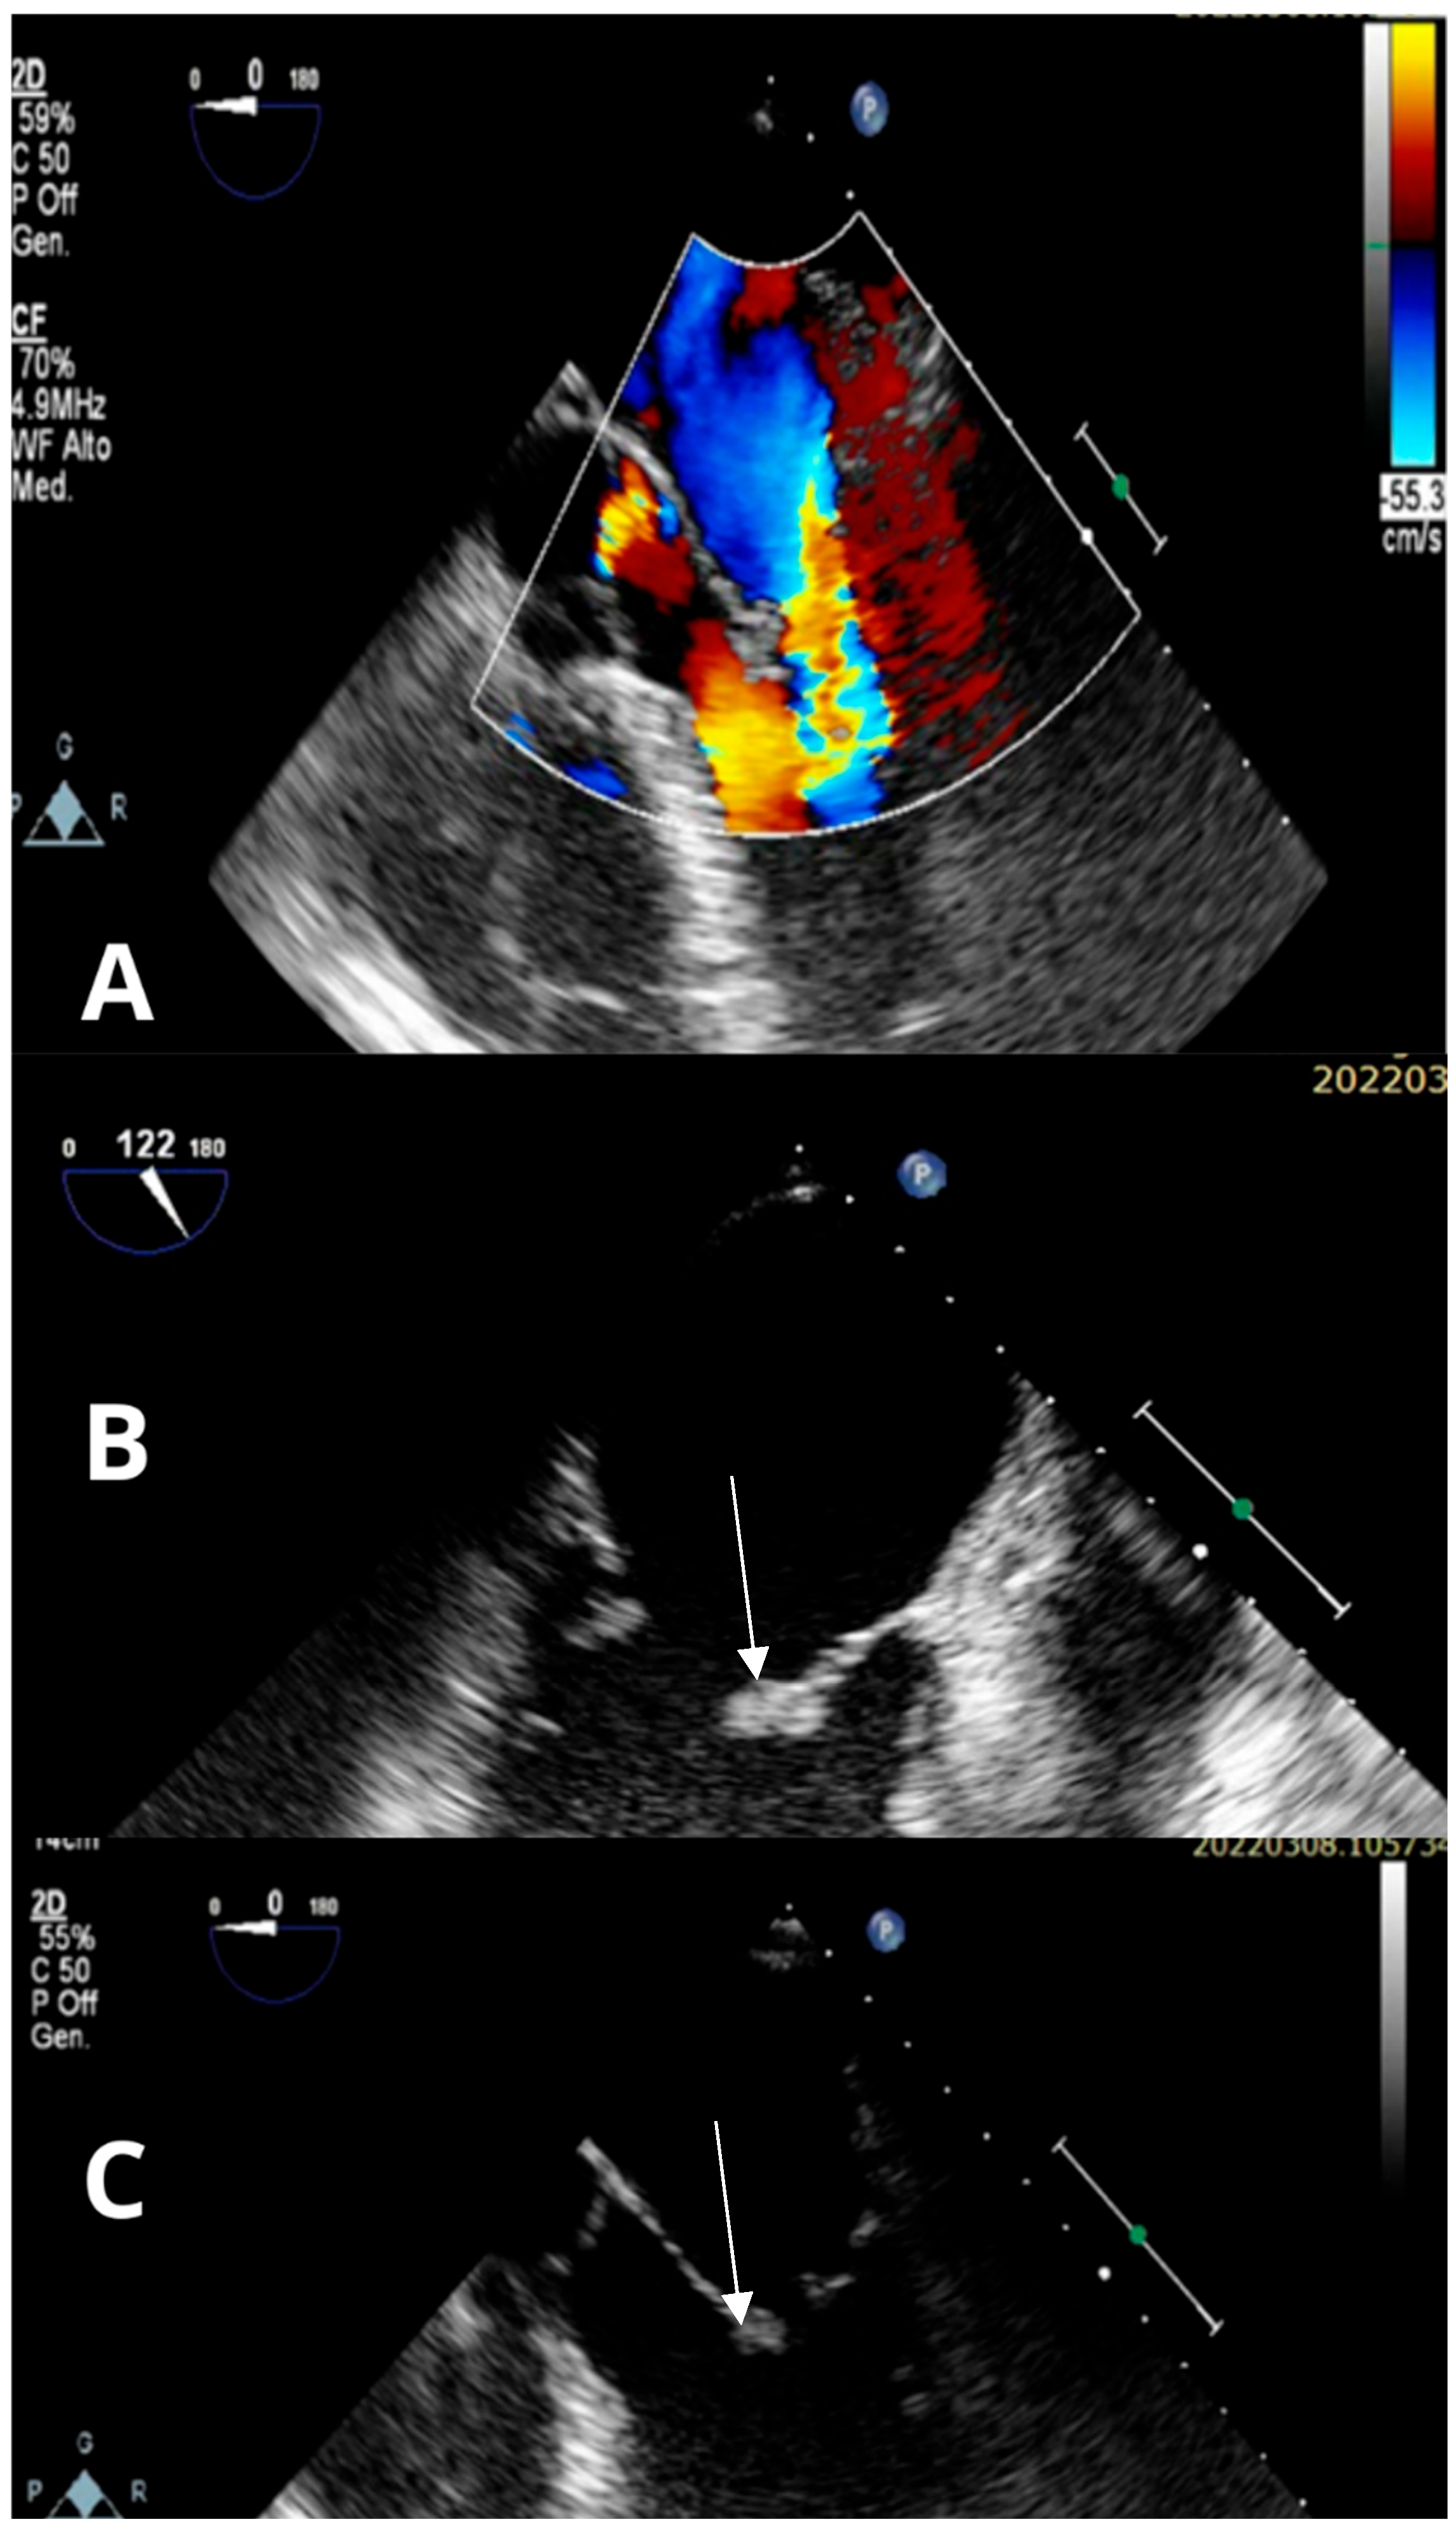

2. Case Presentation